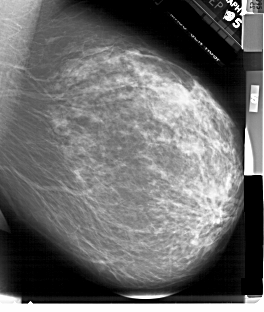

A_1899_1.RIGHT_MLO

LEFT_MLO LINES 6871 PIXELS_PER_LINE 5431 BITS_PER_PIXEL 12 RESOLUTION 43.5 OVERLAY